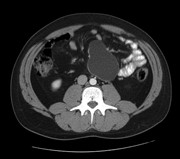

Chylous mesenteric cysts: a rare surgical challenge

Lorenzo Dioscoridi and others

Journal of Surgical Case Reports, Volume 2014, Issue 3, March 2014, rju012, https://doi.org/10.1093/jscr/rju012